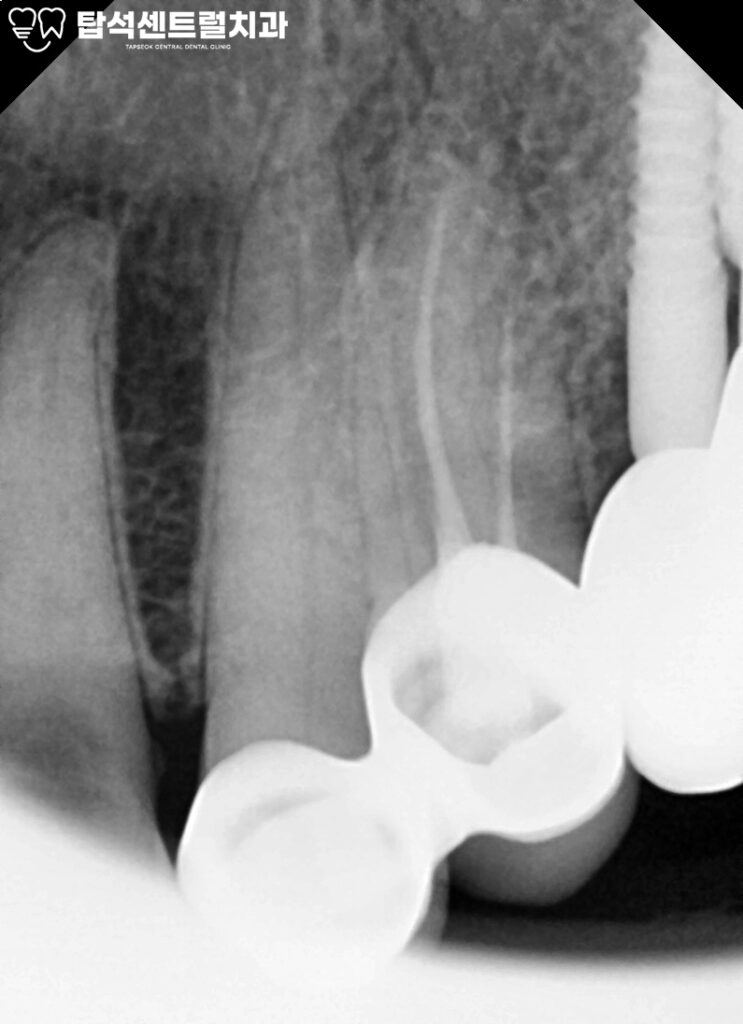

2. 초진 엑스레이

초진 시 파노라마 및 치근단 엑스레이 촬영을 통해

해당 치아의 치근단부 상태와

주변 치조골을 함께 평가하였습니다.

의정부 치과 에서 준비한 영상 상에서 21, 22번 치근단 부위에는

치근단 병소 소견을 관찰되지 않았으며,

주변 치조골 역시 안정적인 상태였습니다.

더불어 자발통, 타진통, 온도 자극에 대한 과민 반응 등

치수 감염을 의심할 만한 임상 반응을 호소하지 않는다면

치수의 생활력이 유지되고 있는 것으로 판단할 수 있습니다.

이때는 불필요한 근관치료를 시행하기보다는

치수 보존을 우선으로 한 보존적 접근을 선택해

근관치료는 보류하기로 결정하였습니다.

다만 임상적으로 확인된 우식 와동의 깊이가 상당하고

치근면까지 확장된 형태를 보이고 있어,

일반적인 레진 수복만으로는

습윤 환경에서의 접착 안정성 저하 및

유지력 부족으로 인해 수복물의 탈락 가능성이

높을 것으로 예상되었습니다.

따라서 단순 수복이 아닌 장기적인 유지력과

변연 적합도를 고려한 재료 선택이

필요하다 판단하였으며,

이에 본 증례에서는 안정적인 접착 성능을

기대할 수 있는 본드필 레진을 이용한 수복을 계획하였습니다.